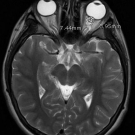

A 13-year-old previously healthy girl with a maternal family history of antiphospholipid syndrome presented with headache, blurry vision, and bilateral papilledema that had been confirmed with MRI and that...